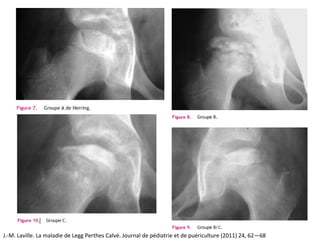

CLASIFICACIÓN RADIOLÓGICA

J.-M. Laville. La maladie de Legg Perthes Calvé. Journal de pédiatrie et de puériculture (2011) 24, 62—68

J.-M. Laville. Lamaladie de Legg Perthes Calvé. Journal de pédiatrie et de puériculture (2011) 24, 62—68